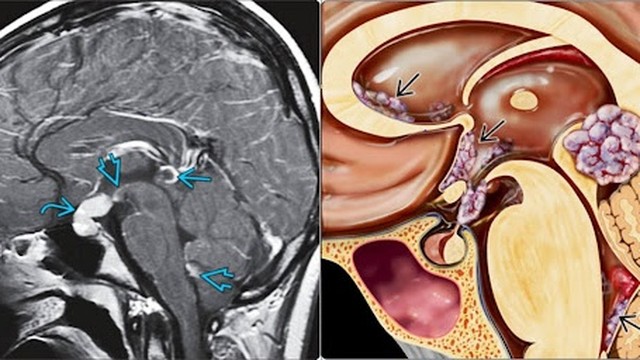

Các u tế bào mầm có thể gặp ở mọi lứa tuổi, nhưng phổ biến nhất ở trẻ em từ 0 - 3 tuổi. Bởi vậy, căn bệnh này rất cần được chẩn đoán kịp thời.